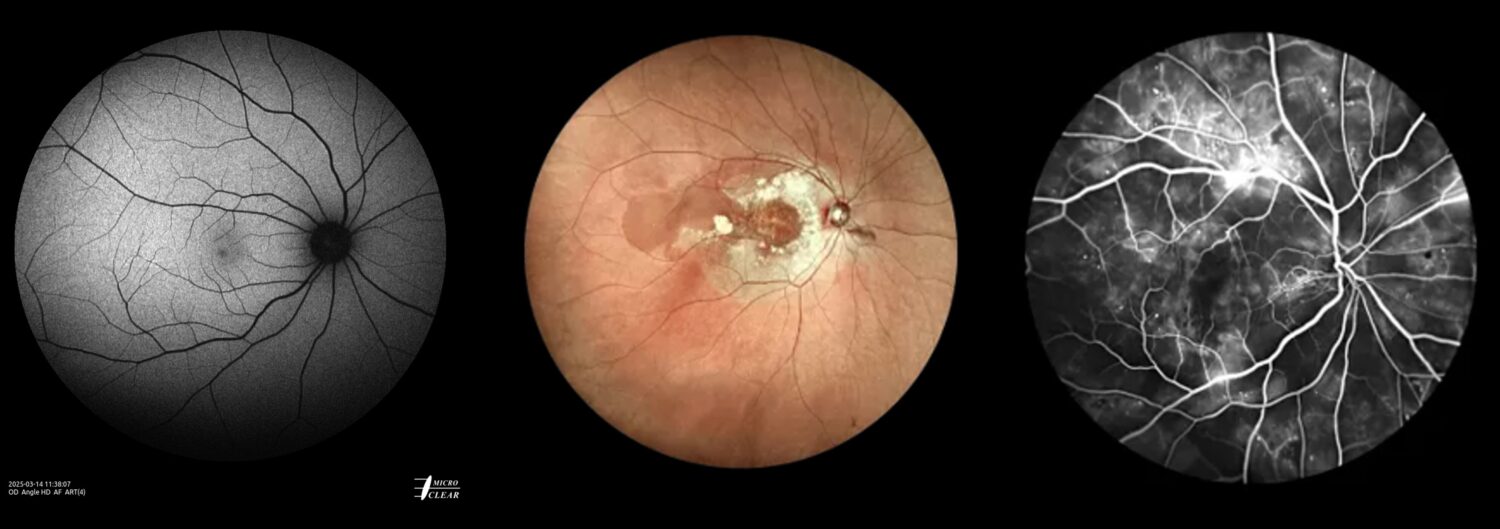

Autofluorescentie wordt steeds populairder als een eenvoudige en niet-invasieve beeldvormingsmethode om de lipofuscineverdeling in kaart te brengen en de gezondheid van het netvlies te monitoren, waardoor netvliespathologieën vroegtijdig kunnen worden opgespoord.

- Multi-color imaging (MC): ‘Confocal SLO’ & ‘SLO based True Color’

- Blauwe en groene fundusautofluorescentie (Blue AF & Green AF)

- Fundusfluoresceïne-angiografie (FFA)

- Roodvrij (RF)